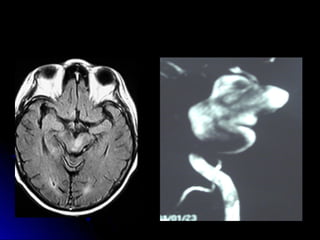

• 34.

Ubicación de laslesiones en TAC-RNM